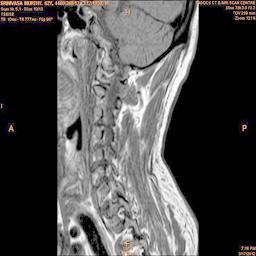

In order to show the proposed method in more detail, the algorithm is tested with other test images. The first row of Fig. 6 shows the original MRI image of thoracic spine with different views. The second row of Fig. 6 shows the same image enhanced using histogram equalization. Third row of Fig. 6 presents the MSR based enhancement scheme. Fourth row of Fig. 6 indicates Chao’s method of image enhancement. Finally, the reconstructed images using the proposed method is shown in fifth row of Fig. 6. Again, it can be seen from the results presented that the image enhancement using the proposed method is superior compared to other methods. This is evident from the image quality assessment presented in Table 1 using AWE and DWE.